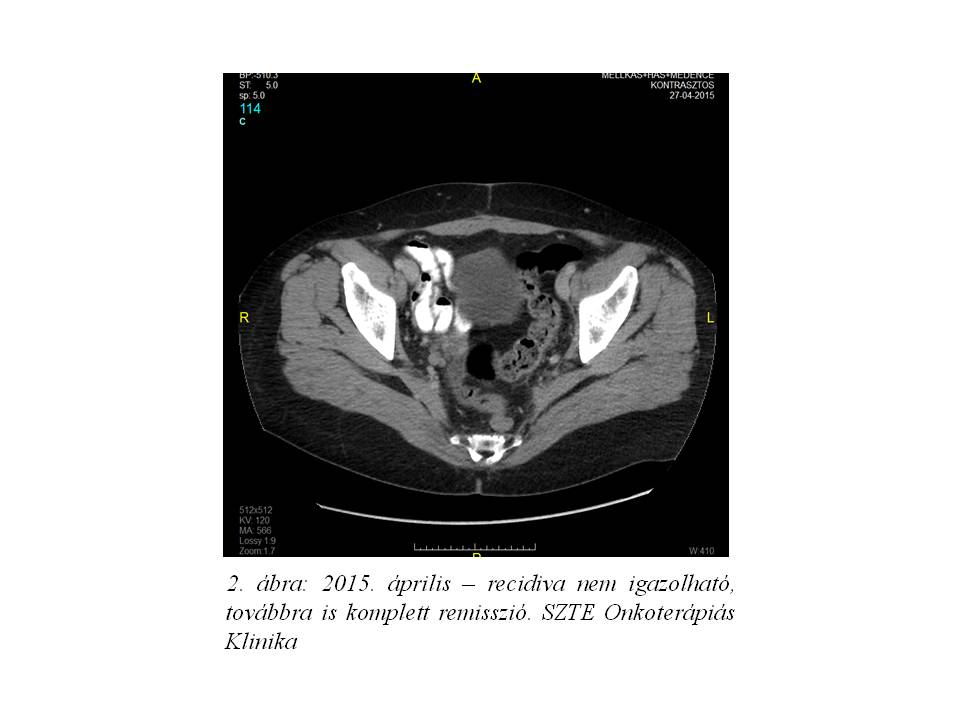

Ismételt onkoteam döntésnek megfelelően a beteg kezelése további három ciklus paclitaxel + carboplatin + bevacizumab posztoperatív immun-kemoterápiával folytatódott. Hat ciklust követően készült re-staging vizsgálatok (képalkotó és tumormarker) komplett remissziót igazoltak. 2015. januártól a kezelése fenntartó, mono-bevacizumab terápiával folytatódott, eddig 12 ciklust komplettálva. Jelenleg betegünk panaszmentes, az áprilisban készült legfrissebb kontroll mellkas+has+medence CT vizsgálat továbbra is tumormentes állapotot írt le, a CEA és CA-125 értékek normál tartományban vannak (2. ábra).